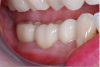

Fig 11 and Fig 12. Final restorations on SLA model.

Figure 11

Figure 12

Fig 13. Initial placement; note tissue deficit on buccal gingival margin of tooth No. 31.

Figure 13

Delivery

Figure 11 and Figure 12 depict the presentation of the model and restoration for delivery. The case was tried in with minimal adjustments, as is typical with most digital cases.20 One consideration at seating was the gingival collar at tooth No. 31 on the buccal. At initial seat, the tissue was noted to be recessed (Figure 13). The author was left with the options of seating temporarily or retuning to the laboratory to address the affected area. It was decided to seat temporarily and allow the tissue to respond. After 3 weeks the patient returned and the tissue had adapted very well. The decision was made to seat more permanently.